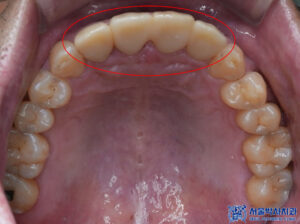

육안으로 확인해 보았을 땐

특별한 이상이 없어

파노라마를 촬영해 보기로 하였습니다.

제거를 하고 확인해 보니,

내부로 충치가 생긴 것을

확인할 수 있었습니다.

앞니는 심미적인 부위이기 때문에,

브릿지의 모양, 색상, 형태를

정밀하게 확인한 후에

영구접착을 진행했습니다.

환자분의 자연스러운 미소를 위해

세심한 조정을 거쳐

최적의 결과를 도출할 수 있도록

신경을 썼습니다.

마무리 후 사진입니다.